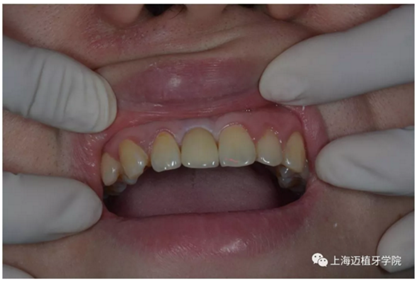

戴牙 最終修復效果